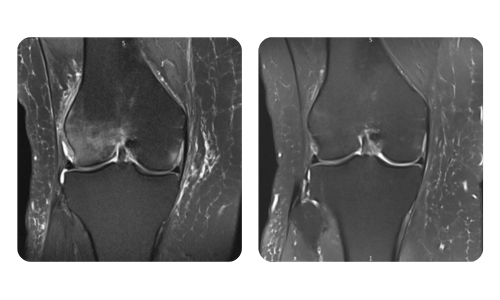

I progressi dei nostri pazienti, misurati prima e dopo la terapia iperbarica, riflettono l'efficacia e l'impatto positivo del trattamento. Scopri i risultati documentati della terapia iperbarica presso la clinica Hyperbarium Oradea, basati su valutazioni cliniche e dati oggettivi che evidenziano miglioramenti significativi in diverse condizioni.